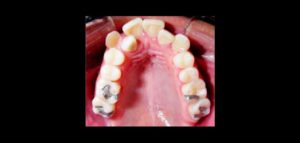

132 – Tratamiento de la reabsorción radicular interna idiopática perforante: controles radiográficos

La reabsorción radicular interna (RRI) es una afección inflamatoria que resulta en la destrucción progresiva de la dentina intra-radicular a lo largo de los tercios